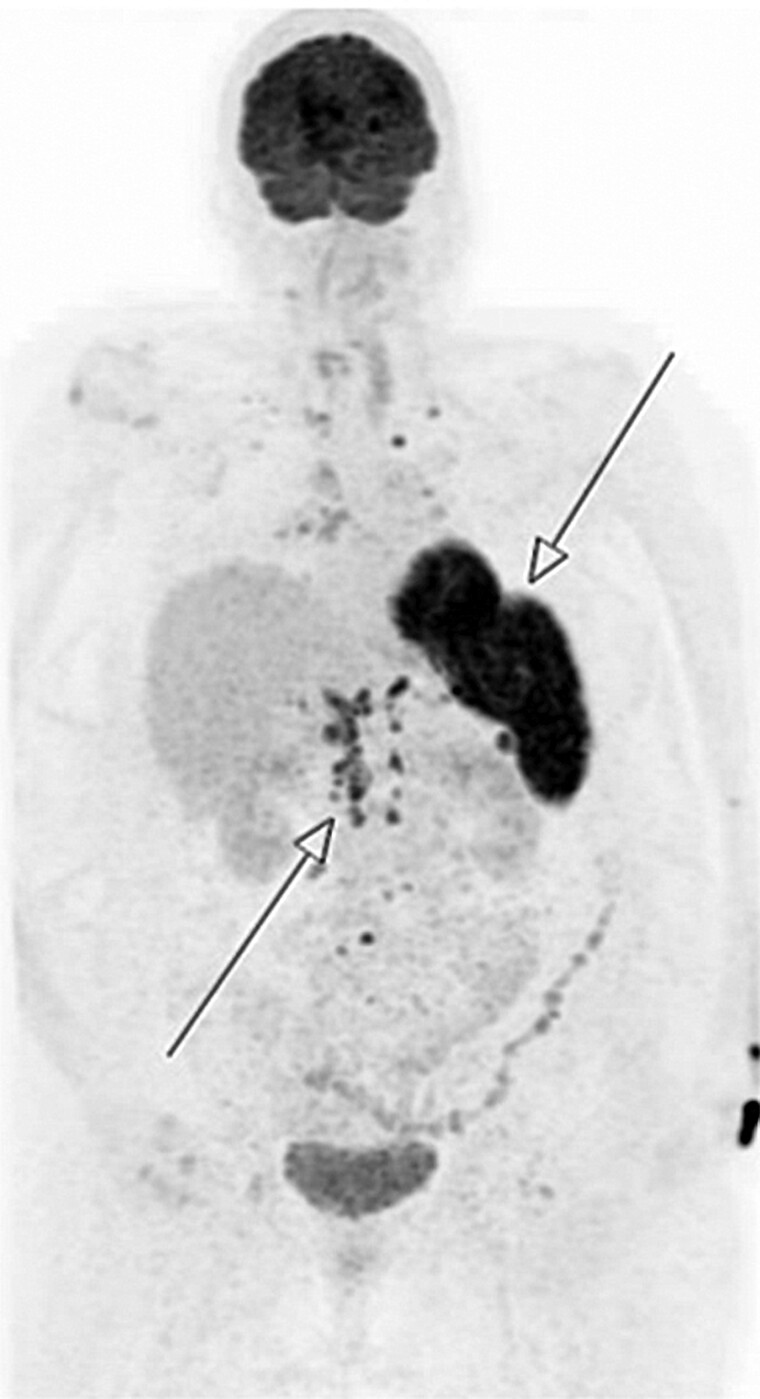

高钙血症在临床实践中经常遇到;然而,结节病引起的高钙血症相对不常见,需要仔细评估,特别是当初步调查不确定或高钙血症难以标准治疗时。我们报告一个复杂的病例,一位60岁的女性患有慢性IV期糖尿病肾病,她表现为脾结节病引起的急性严重无症状高钙血症,脾活检证实。尽管开始了强的松治疗,她的高钙血症仍然存在。静脉输液治疗并发慢性肾脏疾病引起的体液超载。酮康唑作为二线治疗进行试验,没有初步改善。本病例说明了慢性肾损害背景下系统性结节病引起的无症状高钙血症的诊断和治疗挑战。它强调了考虑系统性结节病作为一个潜在病因的重要性,急性甲状旁腺激素非依赖性高钙血症对初始治疗有耐药性。

Hypercalcemia is frequently encountered in clinical practice; however, sarcoidosis-induced hypercalcemia is relatively uncommon and requires careful evaluation, particularly when initial investigations are inconclusive or the hypercalcemia is refractory to standard treatment. We present a complex case of a 60-year-old female with chronic stage IV diabetic nephropathy who presented with acute severe asymptomatic hypercalcemia resulting from splenic sarcoidosis confirmed on splenic biopsy. Despite commencement of prednisone therapy, her hypercalcemia persisted. IV fluid therapy was complicated by fluid overload from chronic renal disease. Ketoconazole was trialed as second-line therapy with no initial improvement. Our case illustrates the diagnostic and therapeutic challenges associated with asymptomatic hypercalcemia attributed to systemic sarcoidosis on a background of chronic renal impairment. It underscores the importance of considering systemic sarcoidosis as a potential etiology in cases of acute PTH-independent hypercalcemia resistant to initial therapy.